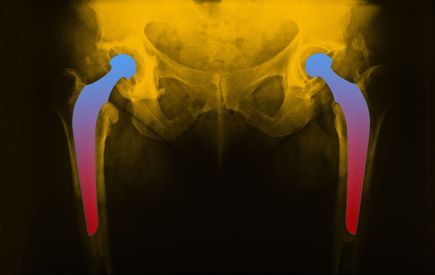

hip-implant-imageHip replacement surgery has improved the quality of life for millions of patients suffering from arthritis or hip fractures.

Yet, hip implants do not come without risks or hip replacement complications. In fact, patients implanted with certain metal-on-metal hip replacement systems may face an increased risk of hip dislocation.

While uncommon, complications following hip implant surgery include hip dislocation, which occurs when the femoral head slips out of the artificial acetabular cup of the hip replacement.

Metal-on-Metal total hip replacement systems are made of a chromium-cobalt alloy and consist of a metal ball (femoral head), a metal femoral stem in the thighbone, and a metal cup in the hip bone (acetabular component).